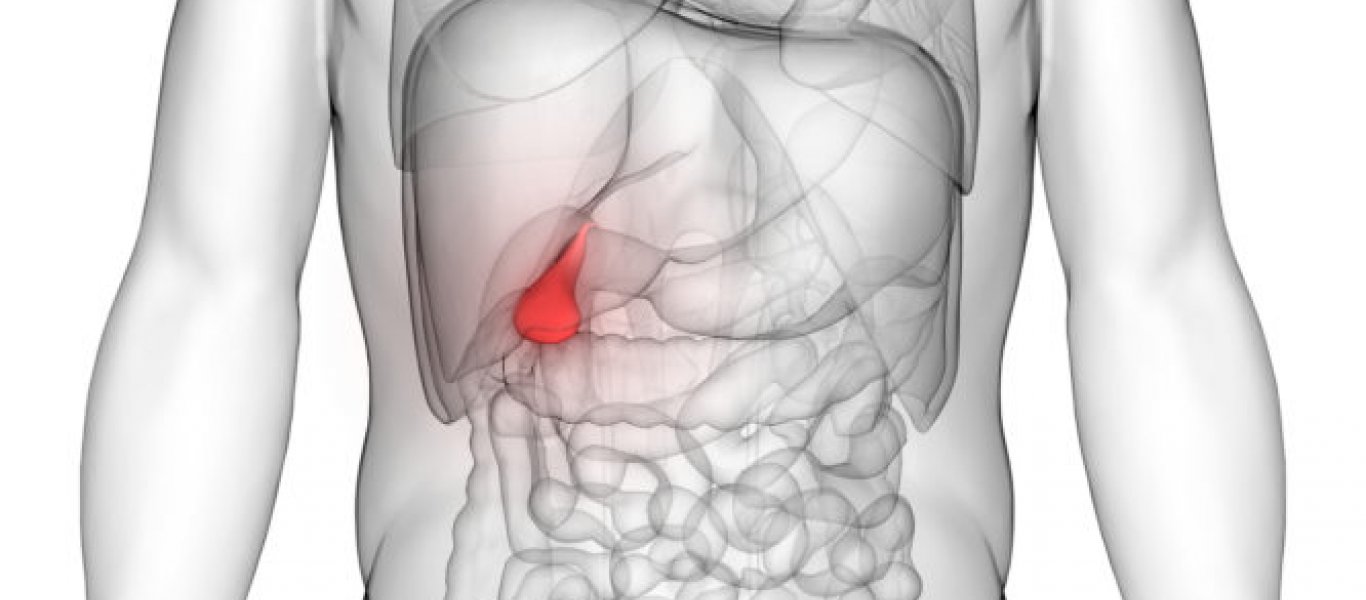

Ελάχιστες είναι οι γνώσεις των περισσοτέρων ανθρώπων για τη χοληδόχο κύστη, παρά το υψηλό ποσοστό του παγκόσμιου πληθυσμού που πάσχει από χολολιθίαση (12%), την πιο συχνή πάθησή της. Οι περισσότεροι δεν ξέρουν ούτε καν που βρίσκεται αυτό το μικρό όργανο, μέχρι τη στιγμή που θα νοιώσουν πόνο στο σημείο. Παρότι ο ρόλος του είναι σημαντικός, όταν προκαλεί συμπτώματα μπορεί να αφαιρεθεί, χωρίς να προκύψουν ουσιαστικά προβλήματα στη λειτουργία του οργανισμού.

«Στη χοληδόχο κύστη, που έχει σχήμα αχλαδιού και βρίσκεται κάτω από το δεξί λοβό του ήπατος, αποθηκεύεται η χολή -που παράγεται από το ήπαρ- πριν απελευθερωθεί στο λεπτό έντερο για να βοηθήσει στην πέψη των λιπών. Το συχνότερο πρόβλημα του οργάνου είναι η δημιουργία χολόλιθων εξαιτίας, κυρίως, της παρατεταμένης παραμονής της χολής στη χοληδόχο κύστη.

Η αφαίρεση της χοληδόχου κύστεως σε ένα κατά τα άλλα υγιές άτομο δεν προκαλεί συνήθως κανένα πρόβλημα. Με λίγα λόγια, οι άνθρωποι μπορούν να ζήσουν και χωρίς τη χοληδόχο κύστη», μας εξηγεί ο γενικός χειρουργός Δρ. Αναστάσιος Ξιάρχος – Διευθυντής της χειρουργικής κλινικής του Ομίλου Ιατρικού Αθηνών – Ιατρικού Περιστερίου και Πρόεδρος της Επιστημονικής Εταιρείας Ορθοπρωκτικής Χειρουργικής (www.axiarchos.gr).